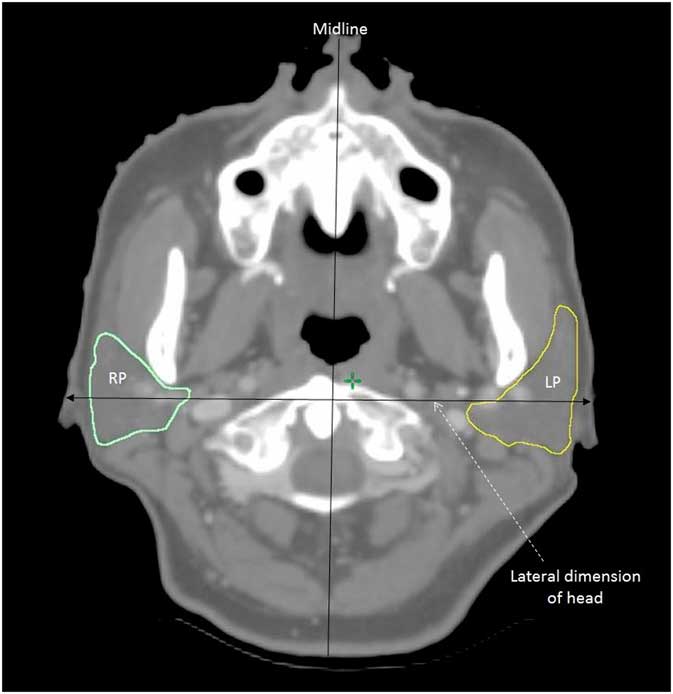

For the assessment of parotid gland changes, percentage change of volume (Δ%V) and dice similarity coefficient (DSC) were obtained. DSC, which indicated the spatial overlap between two volumes,Reference Zou, Warfield and Bharatha 14 was defined by (V o, V s)=2|V o∩V s| / |V o|+|V s|, where V o and V s were the volumes of original parotid gland and subsequent parotid gland at various time intervals, respectively, and ∩ was the intersection. A value of 1·0 would indicate perfect volume match between the two volumes, whereas 0 would imply no overlapping of volume. Translational displacements in x, y and z axes and total vector displacement (TVD), which was the three-dimensional displacement of the centroid, were obtained by comparing the parotid gland in each subsequent CT with that of the original planning CT using the MIM software. In addition to the parotid gland measurement, the change in lateral dimension of the patient’s head (ΔD L) was also measured which was an indication of the patient’s size. The lateral dimension of the patient’s head was defined as the width of the line perpendicular to the mid-line in the CT slice at level of the superior tip of the odontoid process (Figure 1).Reference Cao, Luo and Xu 15 The average values of each measured parameter for the ConRT and IMRT groups were calculated and compared. Normality test was conducted in each set of data. Independent t-test or Mann–Whitney test was conducted dependent on the normality of the data. All statistical tests were performed using Statistical Package for Social Science version 22 (IBM).

Figure 1 A transverse computed tomographic (CT) slice at the level of the tip of odontoid process showing the measurement of lateral dimension of the head.